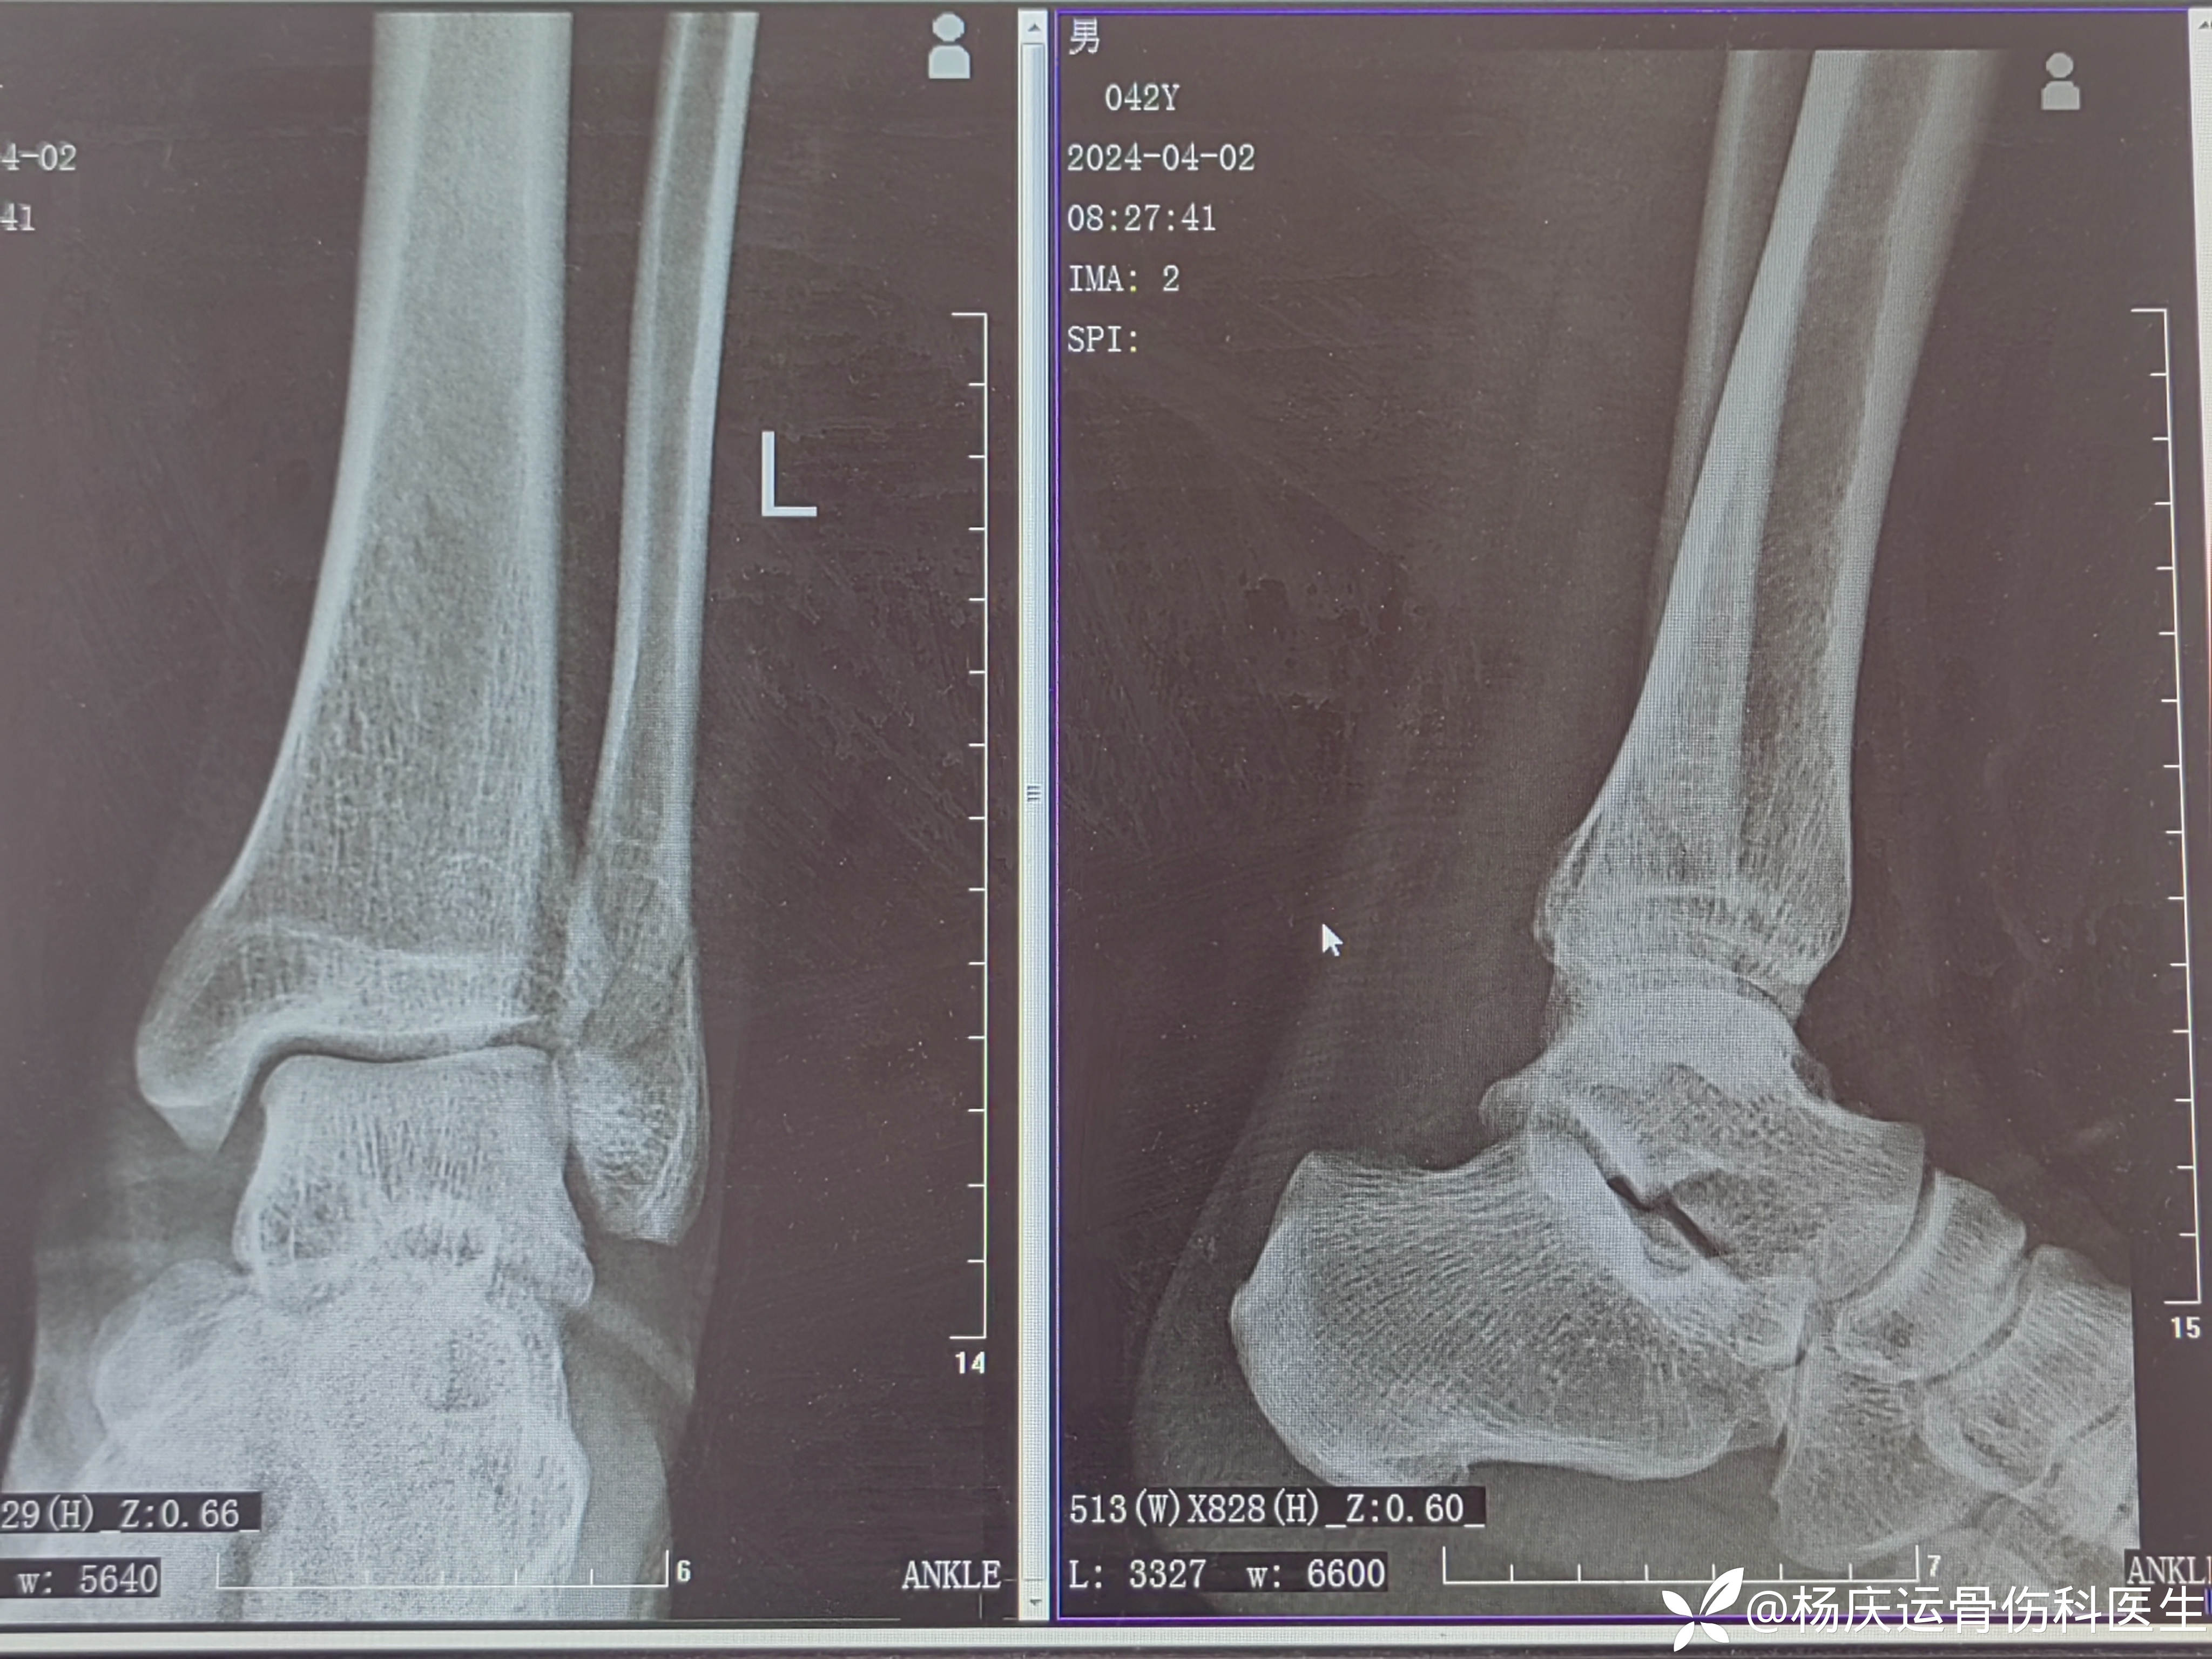

患者商,男,42岁,左踝扭伤肿痛畸形活动受限1小时于2024-3-12来诊。

初步诊断:外后踝骨折伴距骨外脱位 (旋后外旋型IV)

首诊片